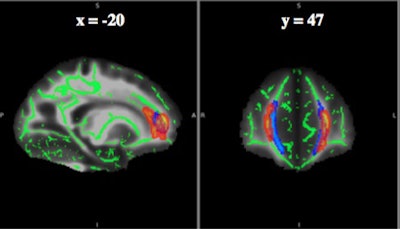

Researchers found lower fractional anisotropy values -- an indication of abnormal movement of water molecules in brain tissue -- in frontal white-matter tracts of nonspeed players, such as offensive and defensive linemen, compared with speed positions, such as quarterbacks, running backs, wide receivers, linebackers, and defensive backs. (Kickers were not included in the study.)

More specifically, fractional anisotropy values varied significantly in three clusters in the forceps minor and genu of the corpus callosum, based on the player's position.

Upon analysis, diffusion-tensor imaging revealed consistently lower fractional anisotropy for nonspeed players with a history of three or more concussions, compared with players with one or no concussions, in the forceps minor and genu of the corpus callosum near the frontal cortex.

"In all three clusters, we see consistent differences in nonspeed players with a high concussion history with lower fractional anisotropy, which has been known to degrade white matter," Champagne said.